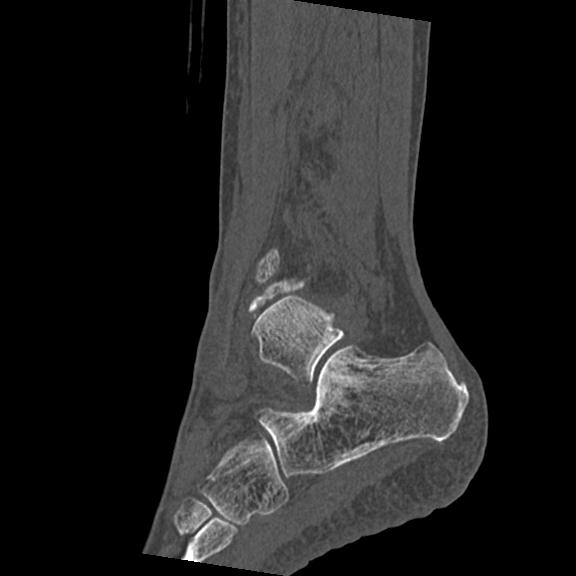

102755 1/4 2R 1/15 2R 右足関節 68歳女性 右三果脱臼骨折